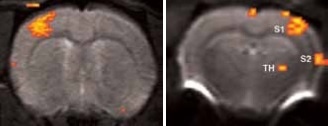

When the forepaw is electrically stimulated, the thalamus, and primary (S1) and secondary (S2) somatosensory corte are activated. To achieve this, electrical pulses (1–2 mA of 0.3 ms duration, at 6 or 3 Hz) are applied for 15 seconds after a resting period of 45 seconds, repeated 5 times. It takes 5 minutes and 45 seconds for the resultant total scan.

Using older DBX electronics and linear surface coils at 7.0 Tesla, BOLD contrast with 400 x 400 x 2000 μm3 resolution can be obtained. Combined with T2-maps, loss of functional activity and its instant recovery as well as stroke lesion (Figure 1) was defined[4,5]. A combination of faster AVANCE II readout electronics, quadrature surface coil, and higher field strength of 11.7 Tesla increased both resolution and SNR to less than 200 x 200 x 2000 μm3, which is more than sufficient to identify the tiny structures along the neuronal activity pathway like the thalamus and secondary somatosensory cortex S2 (Figure 2) with BOLD contrast.

Figure 2. BOLD activation at 11.7 Tesla using the quadrature surface coil with a resolution of (left) 300 x 300 x 2000 μm3 for high quality and (right) 150 x 200 x 2000 μm3 for high sensitivity. Image Credit: Bruker BioSpin Group

Figure 3. High resolution BOLD activation at 11.7 Tesla using the four-element array coil with a resolution of 75 x 75 x 1000 μm3 for detection of (left) sub-structures within S1, and activation within other regions along the neuronal pathway: S2 and thalamus. Image Credit: Bruker BioSpin Group